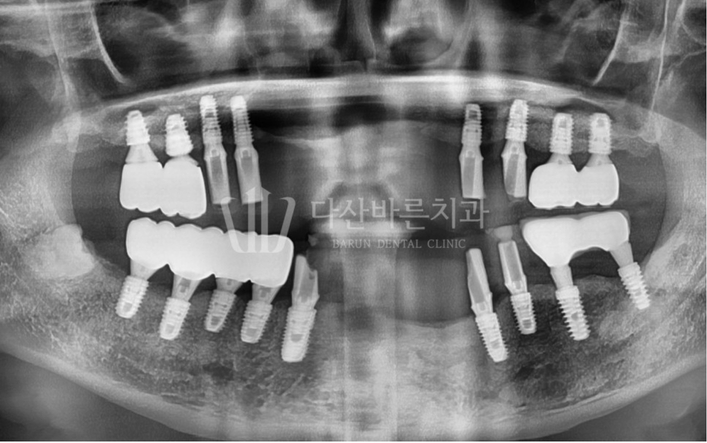

Ảnh dưới đây là ảnh chụp X-quang toàn cảnh quá trình đang điều trị.

Răng cửa hàm trên và hàm dưới đã phải tháo trụ implant do tiêu xương nướu nhiều do viêm quanh implant.

Ngoài ra, việc điều trị cấy ghép implant cũng được thực hiện ở các răng hàm

trên vốn chưa có răng và các răng hàm dưới sẽ rụng tự nhiên trong thời gian sắp tới.

Ngoài ra, một phẫu thuật thẩm mỹ implant đơn giản đã được thực hiện trên implant

hiện có ở phía răng hàm bên trái để ngăn ngừa mất thêm xương nướu.